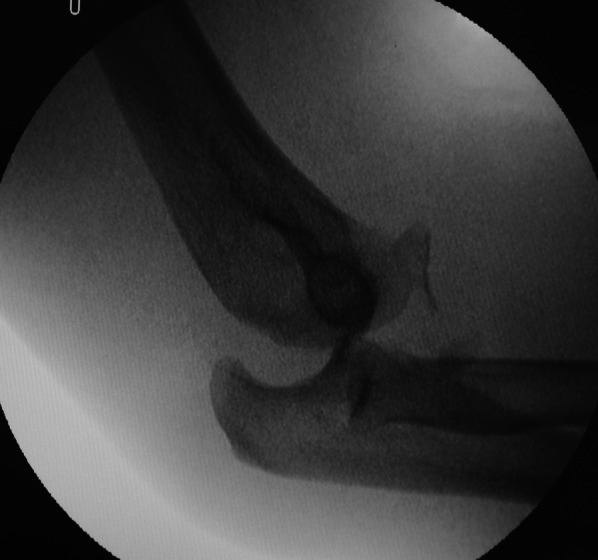

Materials and methods: This prospective observational study included patients with TTIE who exhibited posterior or posterolateral subluxation/dislocation during examination under anesthesia (EUA) at our institute between January 2019 and December 2021. All patients underwent coronoid-first repair through an anterior approach, regardless of fragment size. After CP fixation, radial head fixation/replacement and lateral ulnar collateral ligament repair were performed through the lateral Kocher approach. Radiographic and functional (Mayo Elbow Performance Score [MEPS] and Disabilities of Arm, Shoulder, and Hand score [DASH]) assessments were performed 3, 6, 12, and 24 months after surgery. Complications such as recurrent subluxation/dislocation, synostosis, heterotopic ossification, traumatic arthritis, and stiffness were examined at the follow-up visits.

Results: The analysis included 27 patients. The mean follow-up duration was 29.9 (range 24-44) months. At the 3-, 6-, 12-, and 24-month follow-up, the mean flexion-extension arcs were 88.7° ± 14.7°, 107.9° ± 11.9°, 128.3° ± 15.5°, and 130.9° ± 15.3°; the mean supination-pronation arcs were 143.7° ± 9.9°, 160.4° ± 7.6°, 165.0° ± 6.0°, and 167.9° ± 4.9°; the mean DASH scores were 18.7 ± 5.7, 4.5 ± 6.1, 2.7 ± 6.5, and 2.0 ± 6.8; and the mean MEPS were 79.1 ± 10.3, 90.2 ± 8.3, 94.8 ± 6.6, and 95.9 ± 5.7, respectively. At the 24-month follow-up, 26 patients had excellent and 1 patient had good results according to MEPS. Only one patient had a complication: they exhibited stiffness and did not have a 30-130° flexion-extension arc at 24 months postoperatively.

Conclusions: The EUA findings, rather than fragment size alone, may be a good indicator of whether the CP needs to be repaired. Midterm follow-up results implied that coronoid-first repair through an anterior approach yields satisfactory functional outcomes with minimal complications.